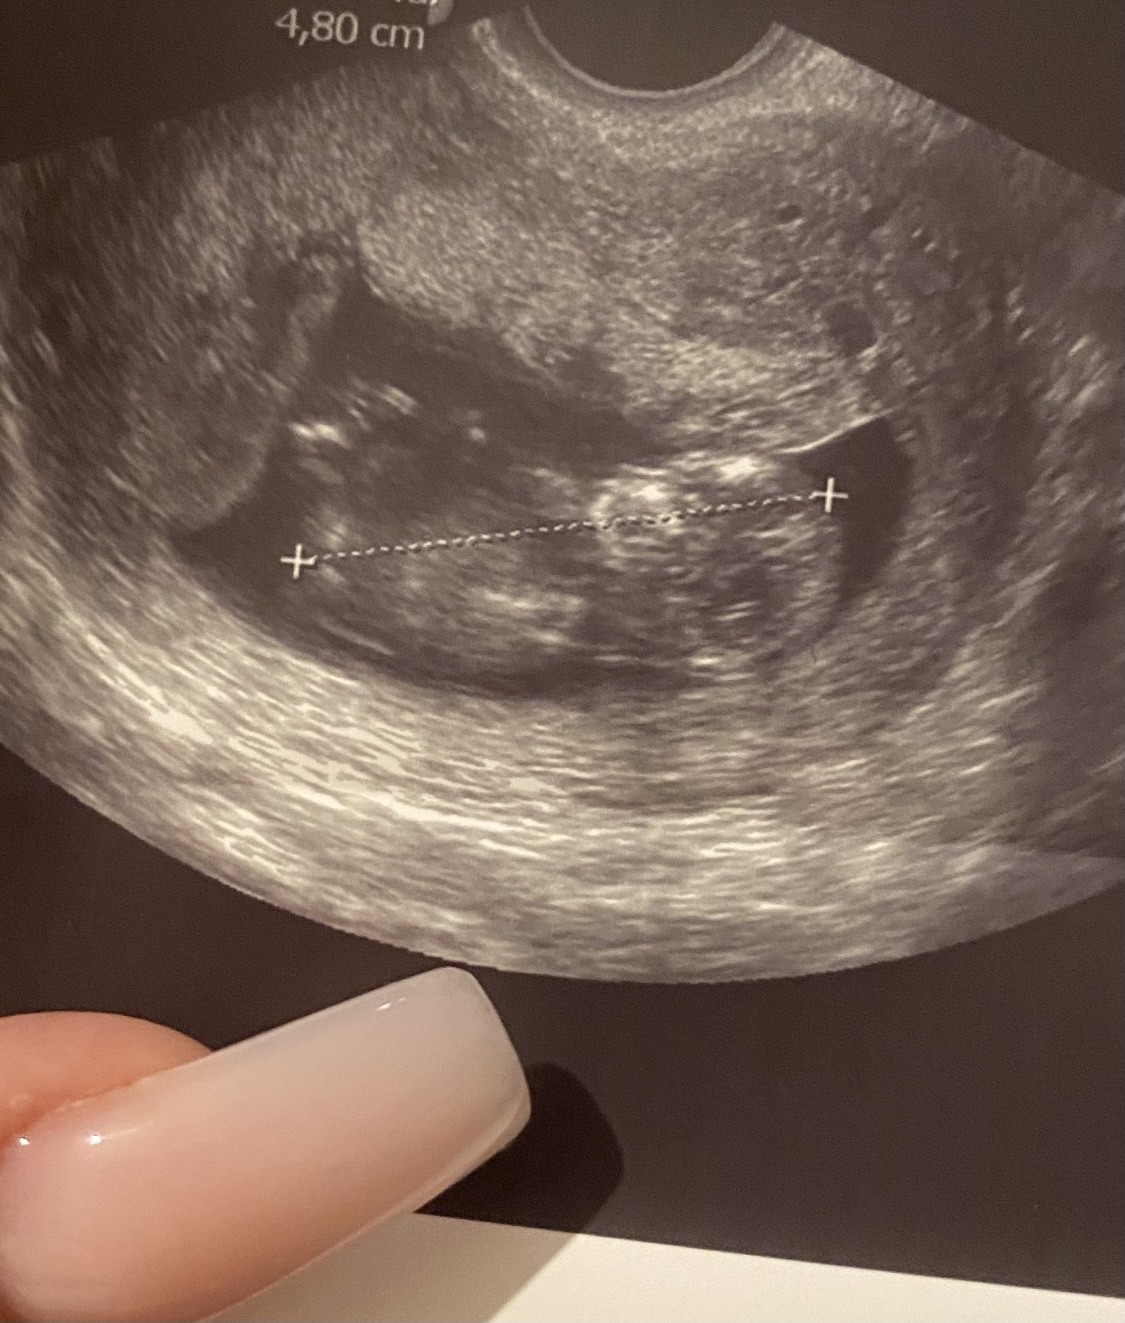

A maluszek rośnie na heparynie jak na drożdżach ❤️😍ma już 1.87cm i wskazuję to na 8t3d 😍temin na 25.10. Serduszko bije 😍to najważniejsze. Następna wizyta 1 kwietnia. Miałam szybką wizytę dzisiaj lekarz dla pewności chciał wyniki zobaczyć i jak ma się maluszek. Powiedział że wszystko rozwija się pieknie 😍